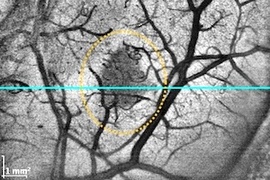

Megahertz OCT improves view of tumor margins and brain anatomy

University of Lübeck integrates faster OCT into commercial neurosurgical microscope.